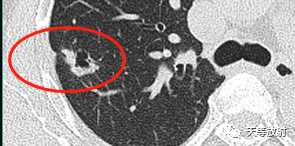

囊腔周围见长条索状影,代表组织受到牵拉聚拢。此时病例的影像学特点:

病变发生于右肺上叶;

实性结节+囊腔

实性略呈分叶状,周围见长条索状影;局部收缩,胸膜凹陷;

囊腔壁厚薄不一。这个结节表现出一定的恶性征象:分叶状实性结节,胸膜凹陷及血管聚拢改变。